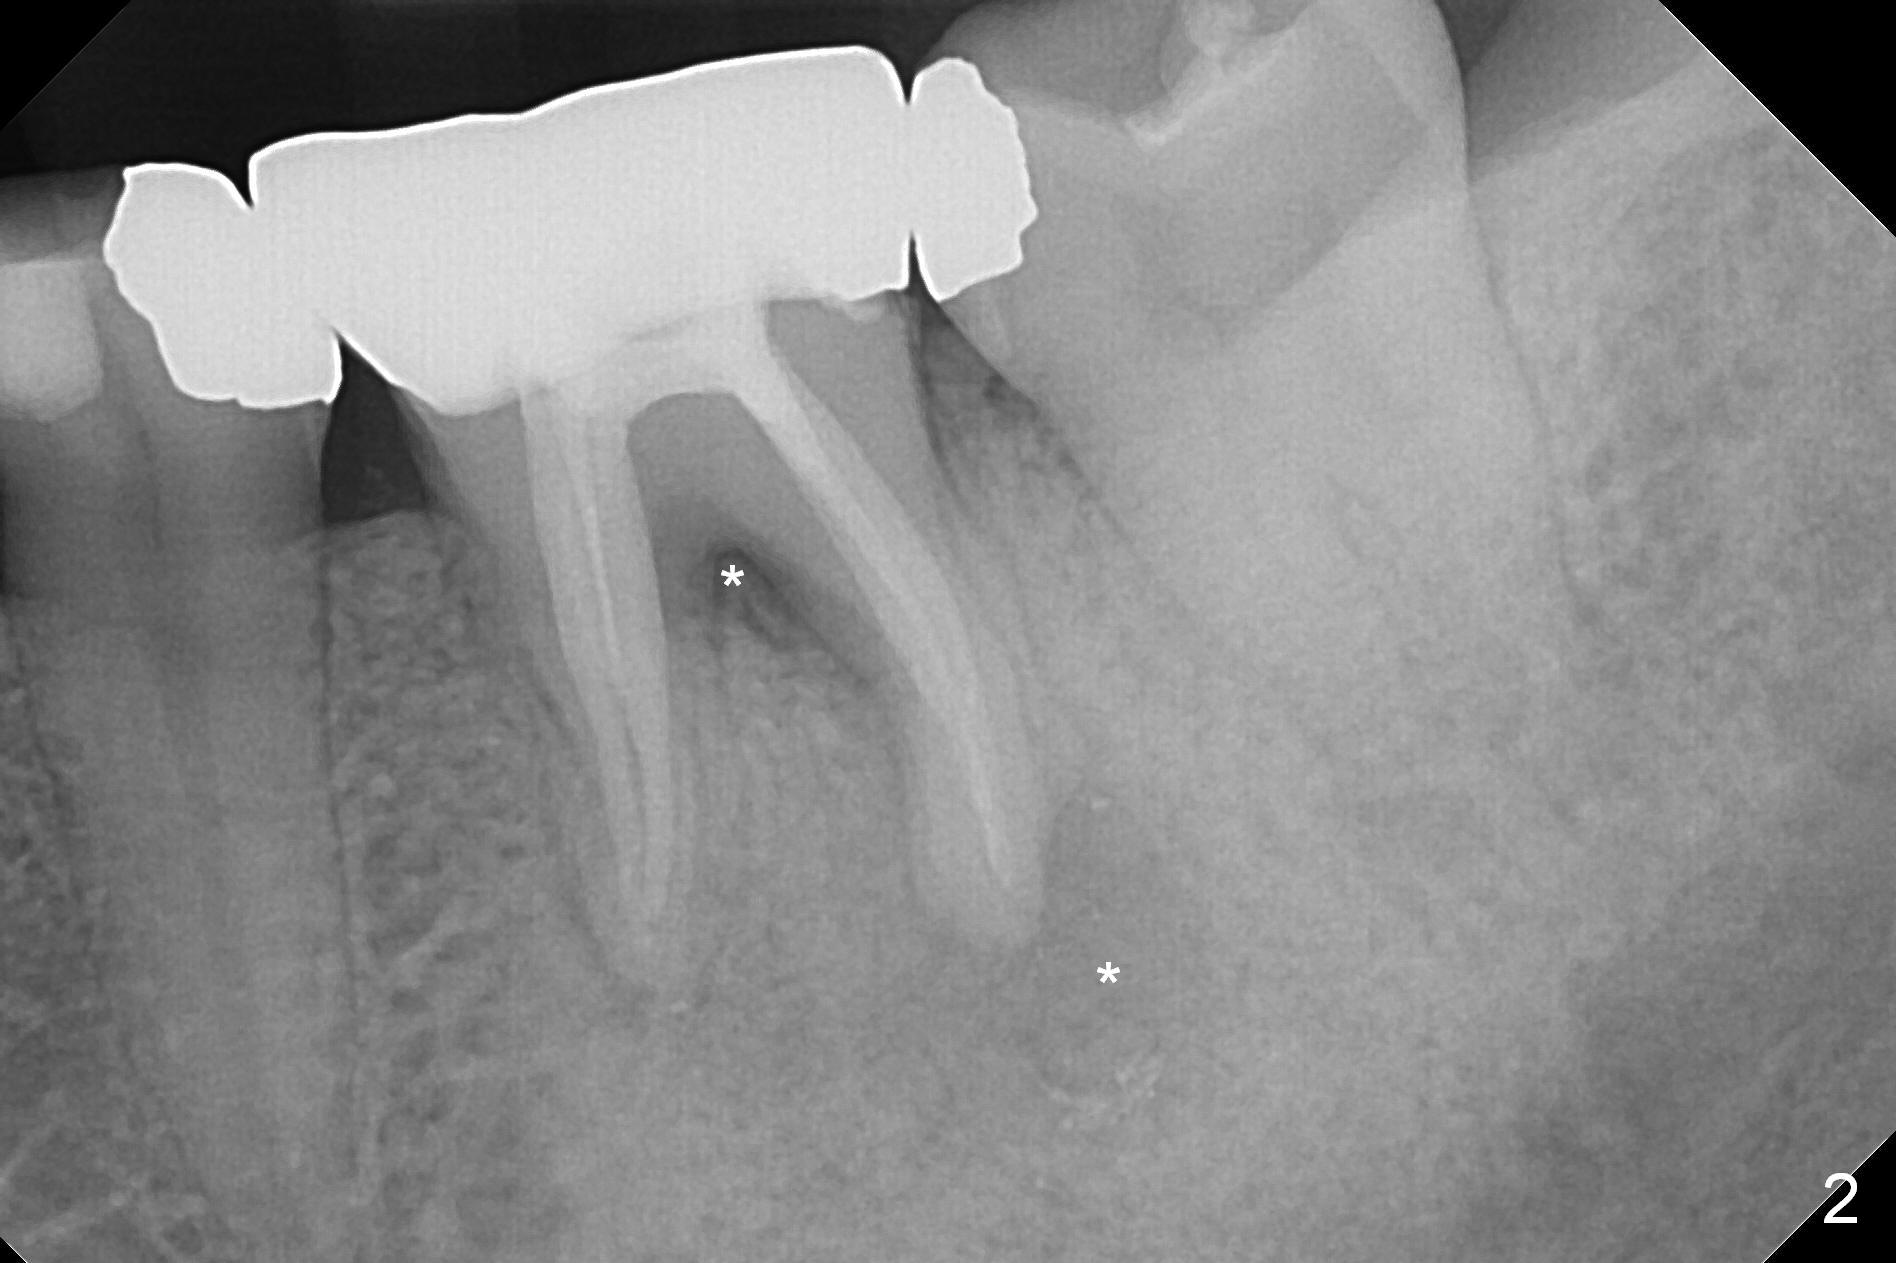

Large Distal Periapical Radiolucency

A 48-year-old woman has had mild discomfort at #19 four years post RCT (Fig.1). It appears that the tooth has 3 roots. The latter should help stabilize an implant placed in the septum (tripods). The affected tooth has large distal periapical radiolucency (Fig,2 *). There is localized swelling at the buccal furca. After debridement, treat the sockets with Clindamycin. Osteotomy will be slightly lingual, since the buccal plate is thinner than the lingual one. In addition, the buccal plate is most likely defective due to furca and periapical lesions. The longest IBS implant is going to be chosen unless the implant has to be placed deep due to furca destruction. In fact the patient has the tooth extracted in other office with socket preservation.